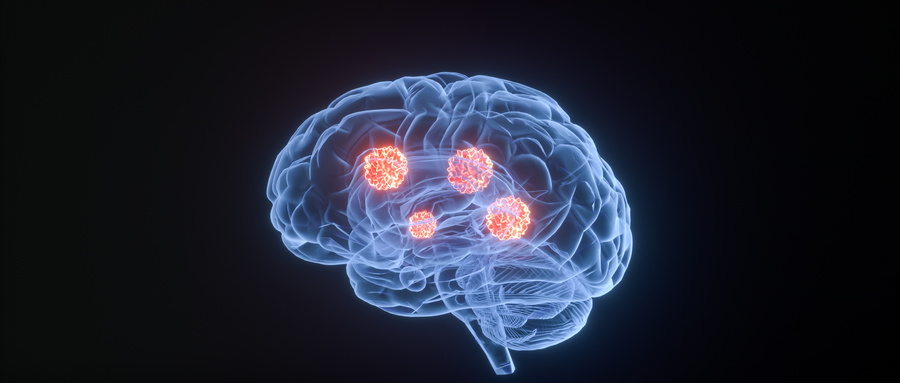

脑瘤是非常严重的脑部疾病,一旦出现了脑瘤疾病我们需要科学的治疗。脑瘤的治疗方案选择:  1、直接手术切除;手术时机和进路应根据患眼视力、肿瘤原发位置、范围以及年龄和健康状况来确定。原则上应争取完全切除,...【全文】

脑瘤是指生长于颅内的肿瘤,可发生于任何年龄。常常会出现头痛、恶心、呕吐、头痛等症状。那么在生活中,我们应该如何预防呢?听听全球医院网专家怎么说。一、生活要有规律生活要规律,生活习惯不规律的人,如彻夜唱...【全文】

• 大叔最易中招脑瘤

脑子里长瘤是件恐怖的事儿,老百姓俗称的“脑癌”就是脑胶质瘤,偏偏“钟爱”四五十岁的中年大叔。脑胶质瘤在原发性脑瘤中发病率居首位,成为除胰腺癌之外死亡率最高的癌症,也最易侵袭中年男性。  脑胶质瘤是最为...【全文】